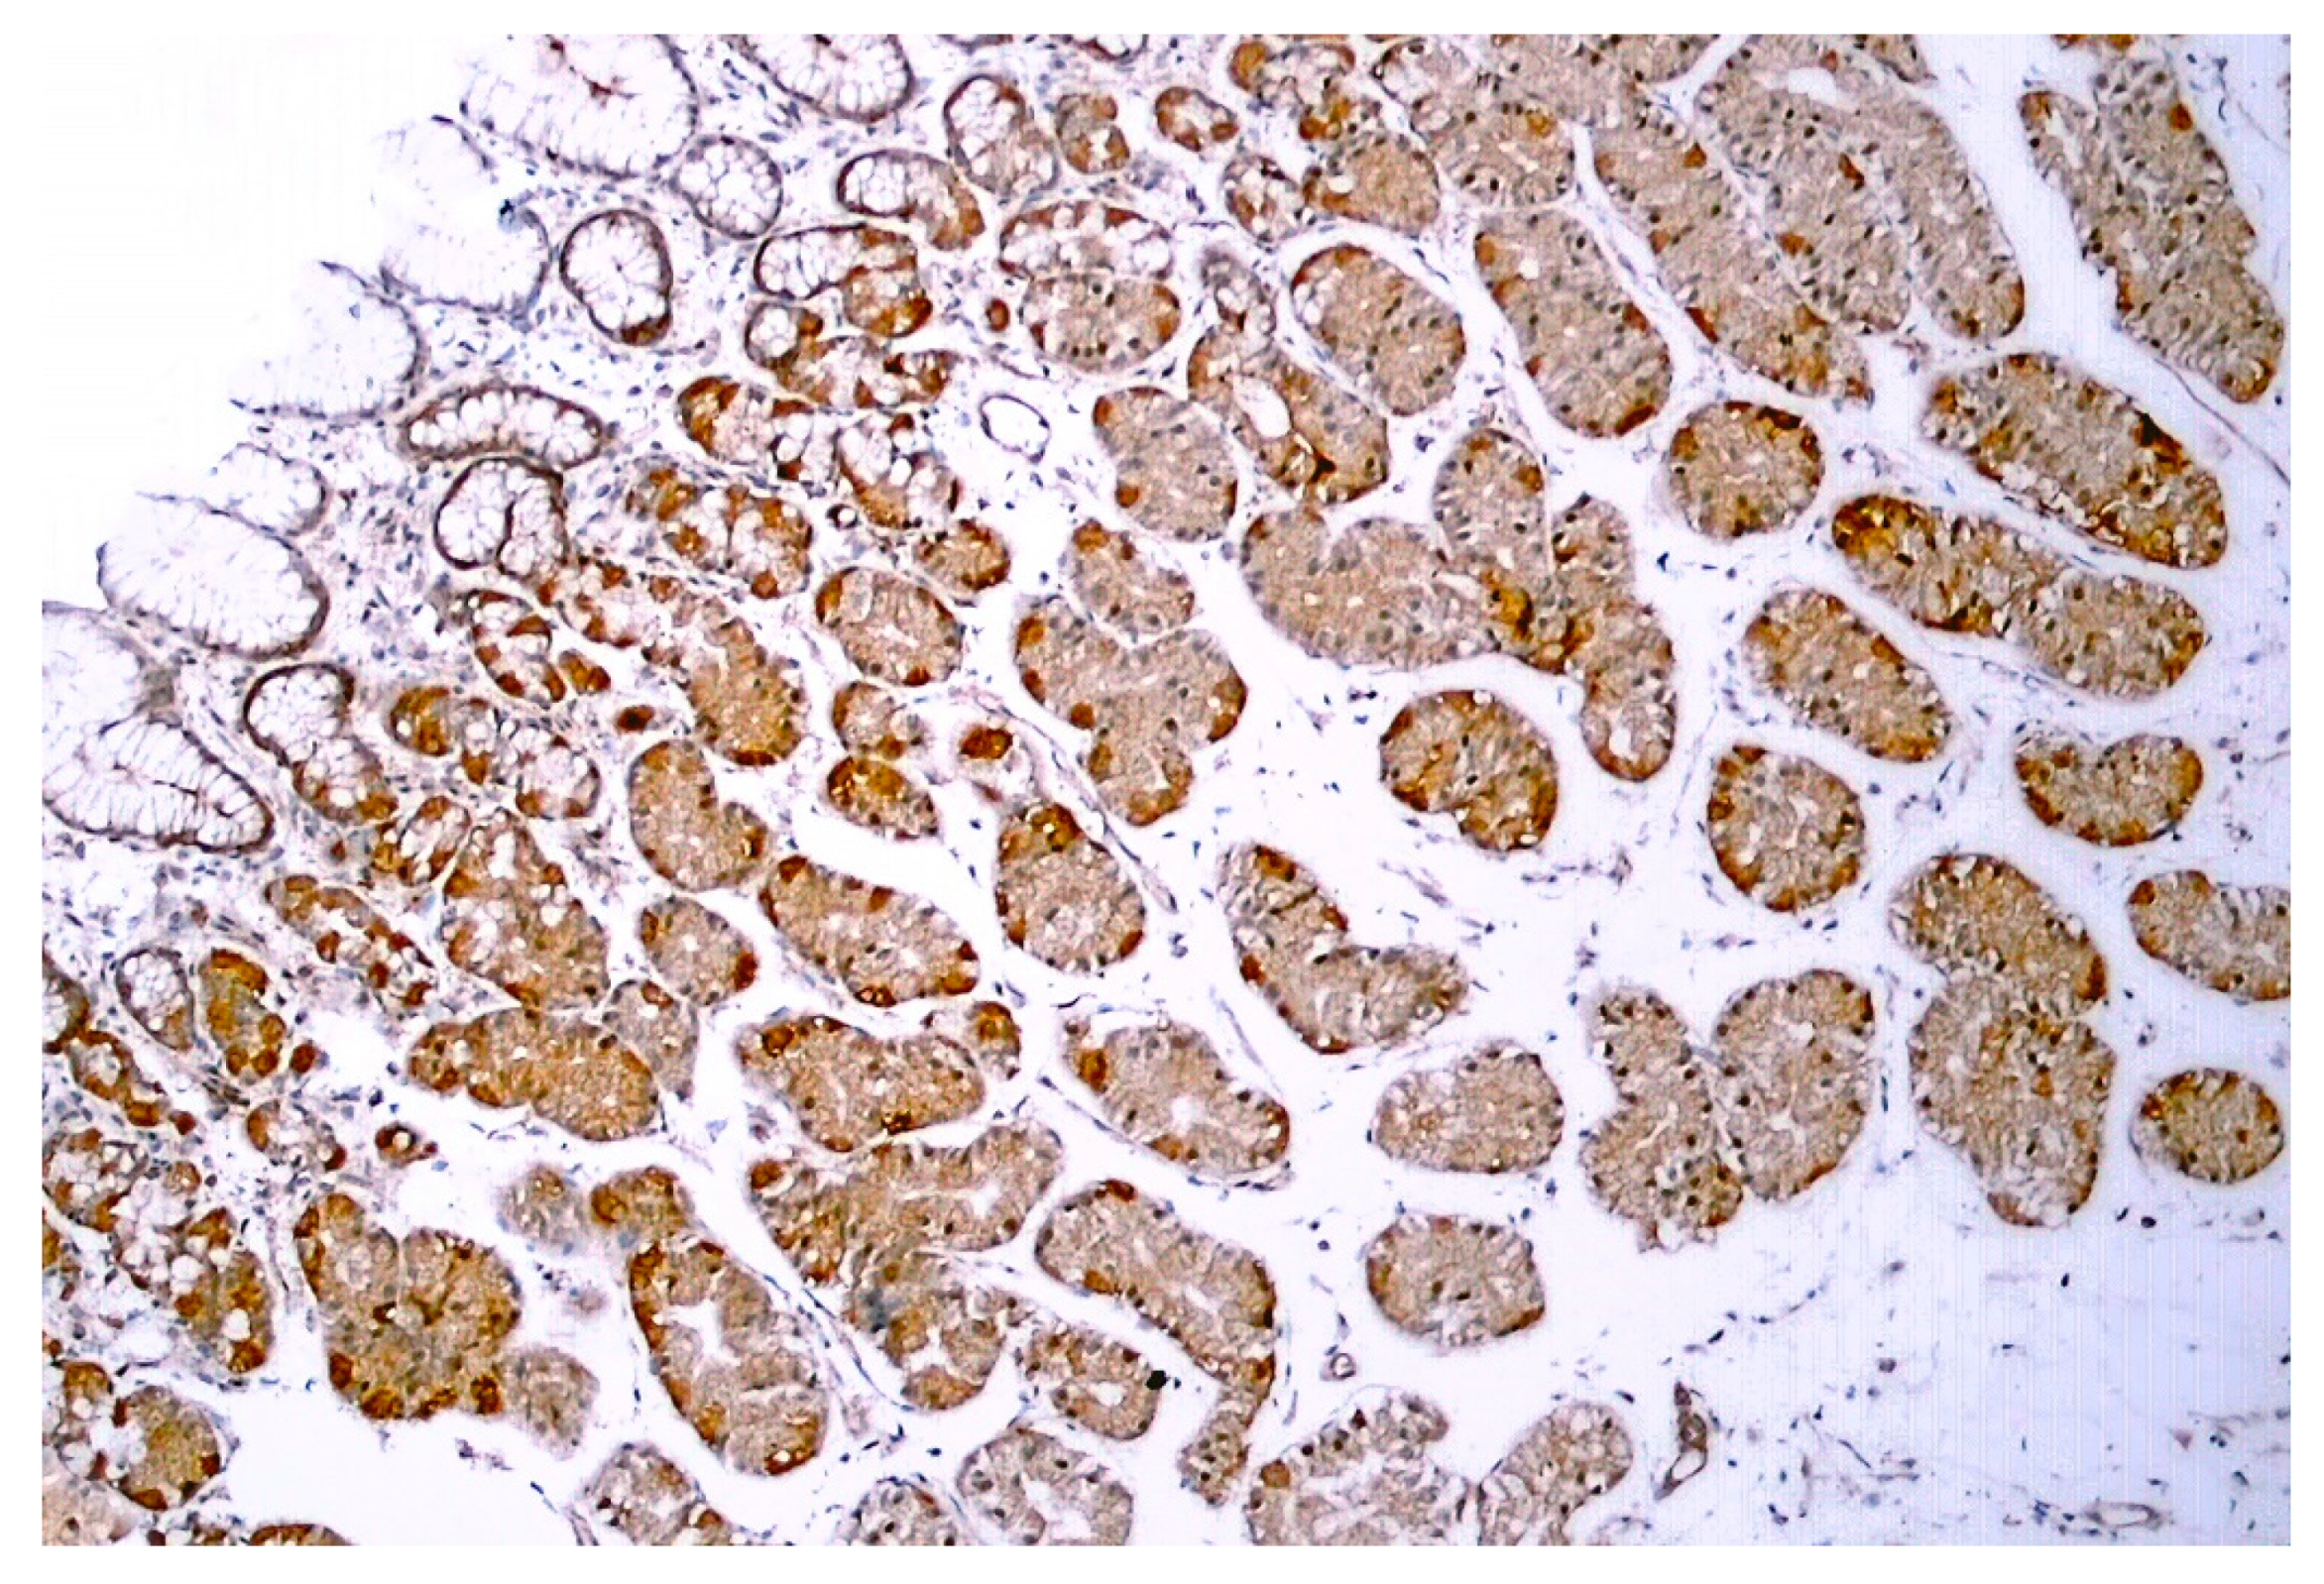

Figure 5.

TRPV1-like immunoreactivity in human gastric biopsy (normal body weight individual). Figure courtesy of Dr. Gülsüm Özlem Elpek, Akdeniz University, Turkey.